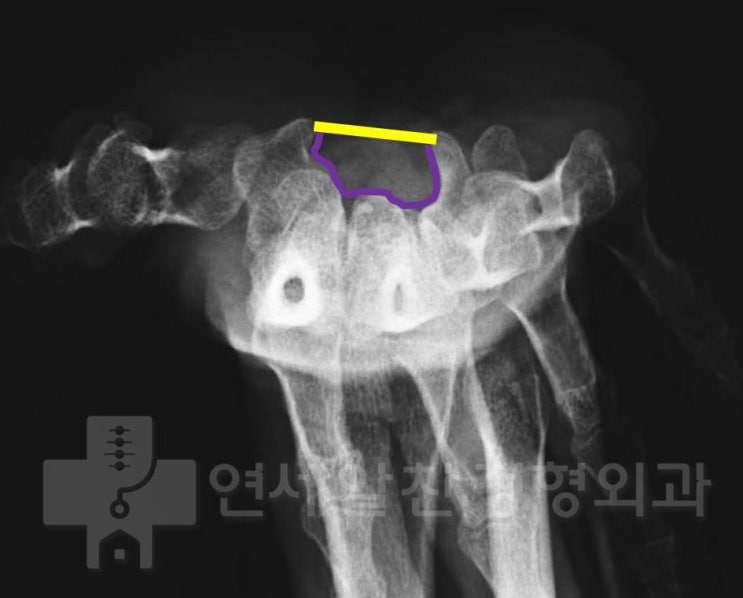

관절와순에 발생된 석회성 건염. 진단 및 치료에 대한 고찰

석회성 건염은 매우 통증이 심한 질환입니다. 대부분 회전근개 내에 발생되는 경우가 많습니다. 힘줄에 발...